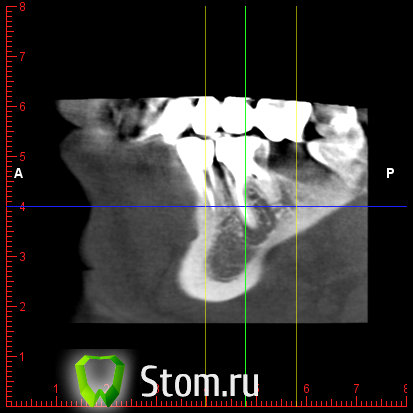

y2006 Опубликовано 3 мая, 2012 Автор Поделиться Опубликовано 3 мая, 2012 (изменено) прошу проконсультировать по поводу зуба 46. вопрос стоит в лечении и протезировании коронкой или удалении и заменой имплантом, правда ли что есть показания к удалению - перфорация корня? файлы для Romexis_Viewer по ссылке: (чуть позже)к сожалению не знаю как по другому выложить Изменено 3 мая, 2012 пользователем y2006 Ссылка на комментарий

y2006 Опубликовано 3 мая, 2012 Автор Поделиться Опубликовано 3 мая, 2012 снимок Ссылка на комментарий

y2006 Опубликовано 3 мая, 2012 Автор Поделиться Опубликовано 3 мая, 2012 (изменено) какие есть методы лечения? или есть необходимость в дополнительных проекциях? Изменено 3 мая, 2012 пользователем y2006 Ссылка на комментарий

y2006 Опубликовано 5 мая, 2012 Автор Поделиться Опубликовано 5 мая, 2012 (изменено) КТ IMAGES.rar46 зуб Изменено 5 мая, 2012 пользователем y2006 Ссылка на комментарий